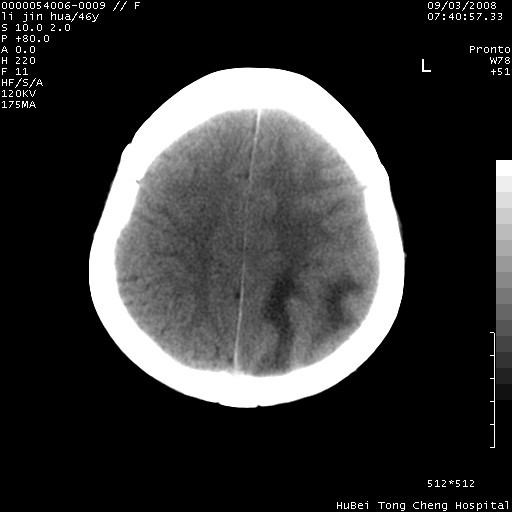

以下是引用panyishengct在2008-9-6 1:47:00的发言:[br]病史?[br]左侧枕/顶叶见一等/低混杂密度占位,壁完整,厚薄较均匀,其前方似有一类似小病灶,周围有水肿带,请结合病史考虑,脓肿可能,不排外转移瘤或胶质瘤,建议增强扫描。